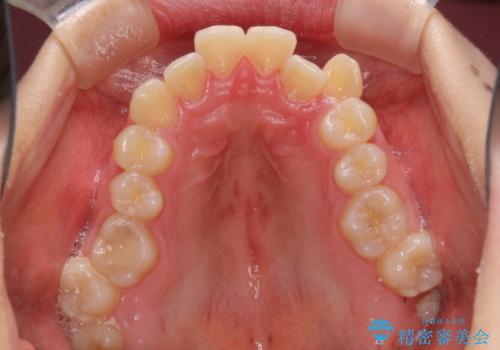

インビザラインによる矯正治療を希望されたため、上顎歯列の側方拡大奥歯の遠心移動のための補助装置を併用し、その後はインビザラインにて行うこととしました。

八重歯の動きが鈍く、治療期間は長期化しました。

癒着の疑いもありましたが、アンカースクリューを多用し、何とか改善することができました。